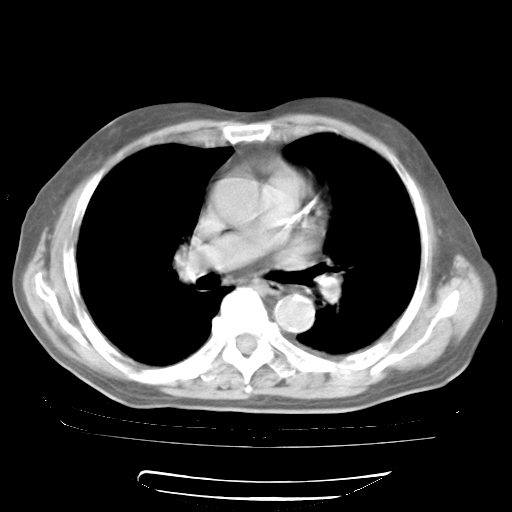

4月28日肺部CT

个人阅读4.14日肺部CT平扫:纵隔窗无异常,但肺窗示:双下肺内、后基底段有片絮状侵润影,部位以后基底段为著,以间质改变为主,呈急性肺泡炎征像,和首次住院影像学有相似之处。仅是个人读片,明日请相关专家再读片哈。其它建议同上。

今请临免主任会诊后认为:4月14日胸部CT已有双下肺间质性改变。患者病情复发多系激素减量过快不正规所致。目前甲强龙80mg/日,一周后酌情开始减量,不易过快。环磷酰胺若已停用,暂不使用。他同意目前抗菌药物使用,但应考虑是否加用B-内酰胺类抗菌药物(中性细胞明显增高);2、结核复发目前依据不足;3、若免疫全套各项指标正常,考虑多系特发性肺间质炎可能大。4、加强支持,并注意保护胃黏膜。